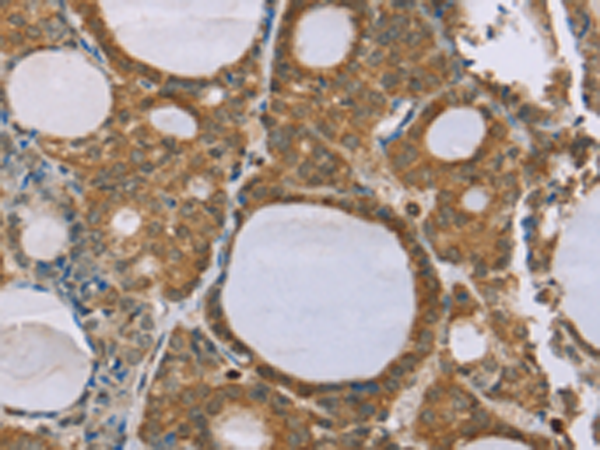

分类: 科研抗体货号: P12145别名: PYY1; PYY-I应用: IHC反应种属: Human, Mouse, Rat